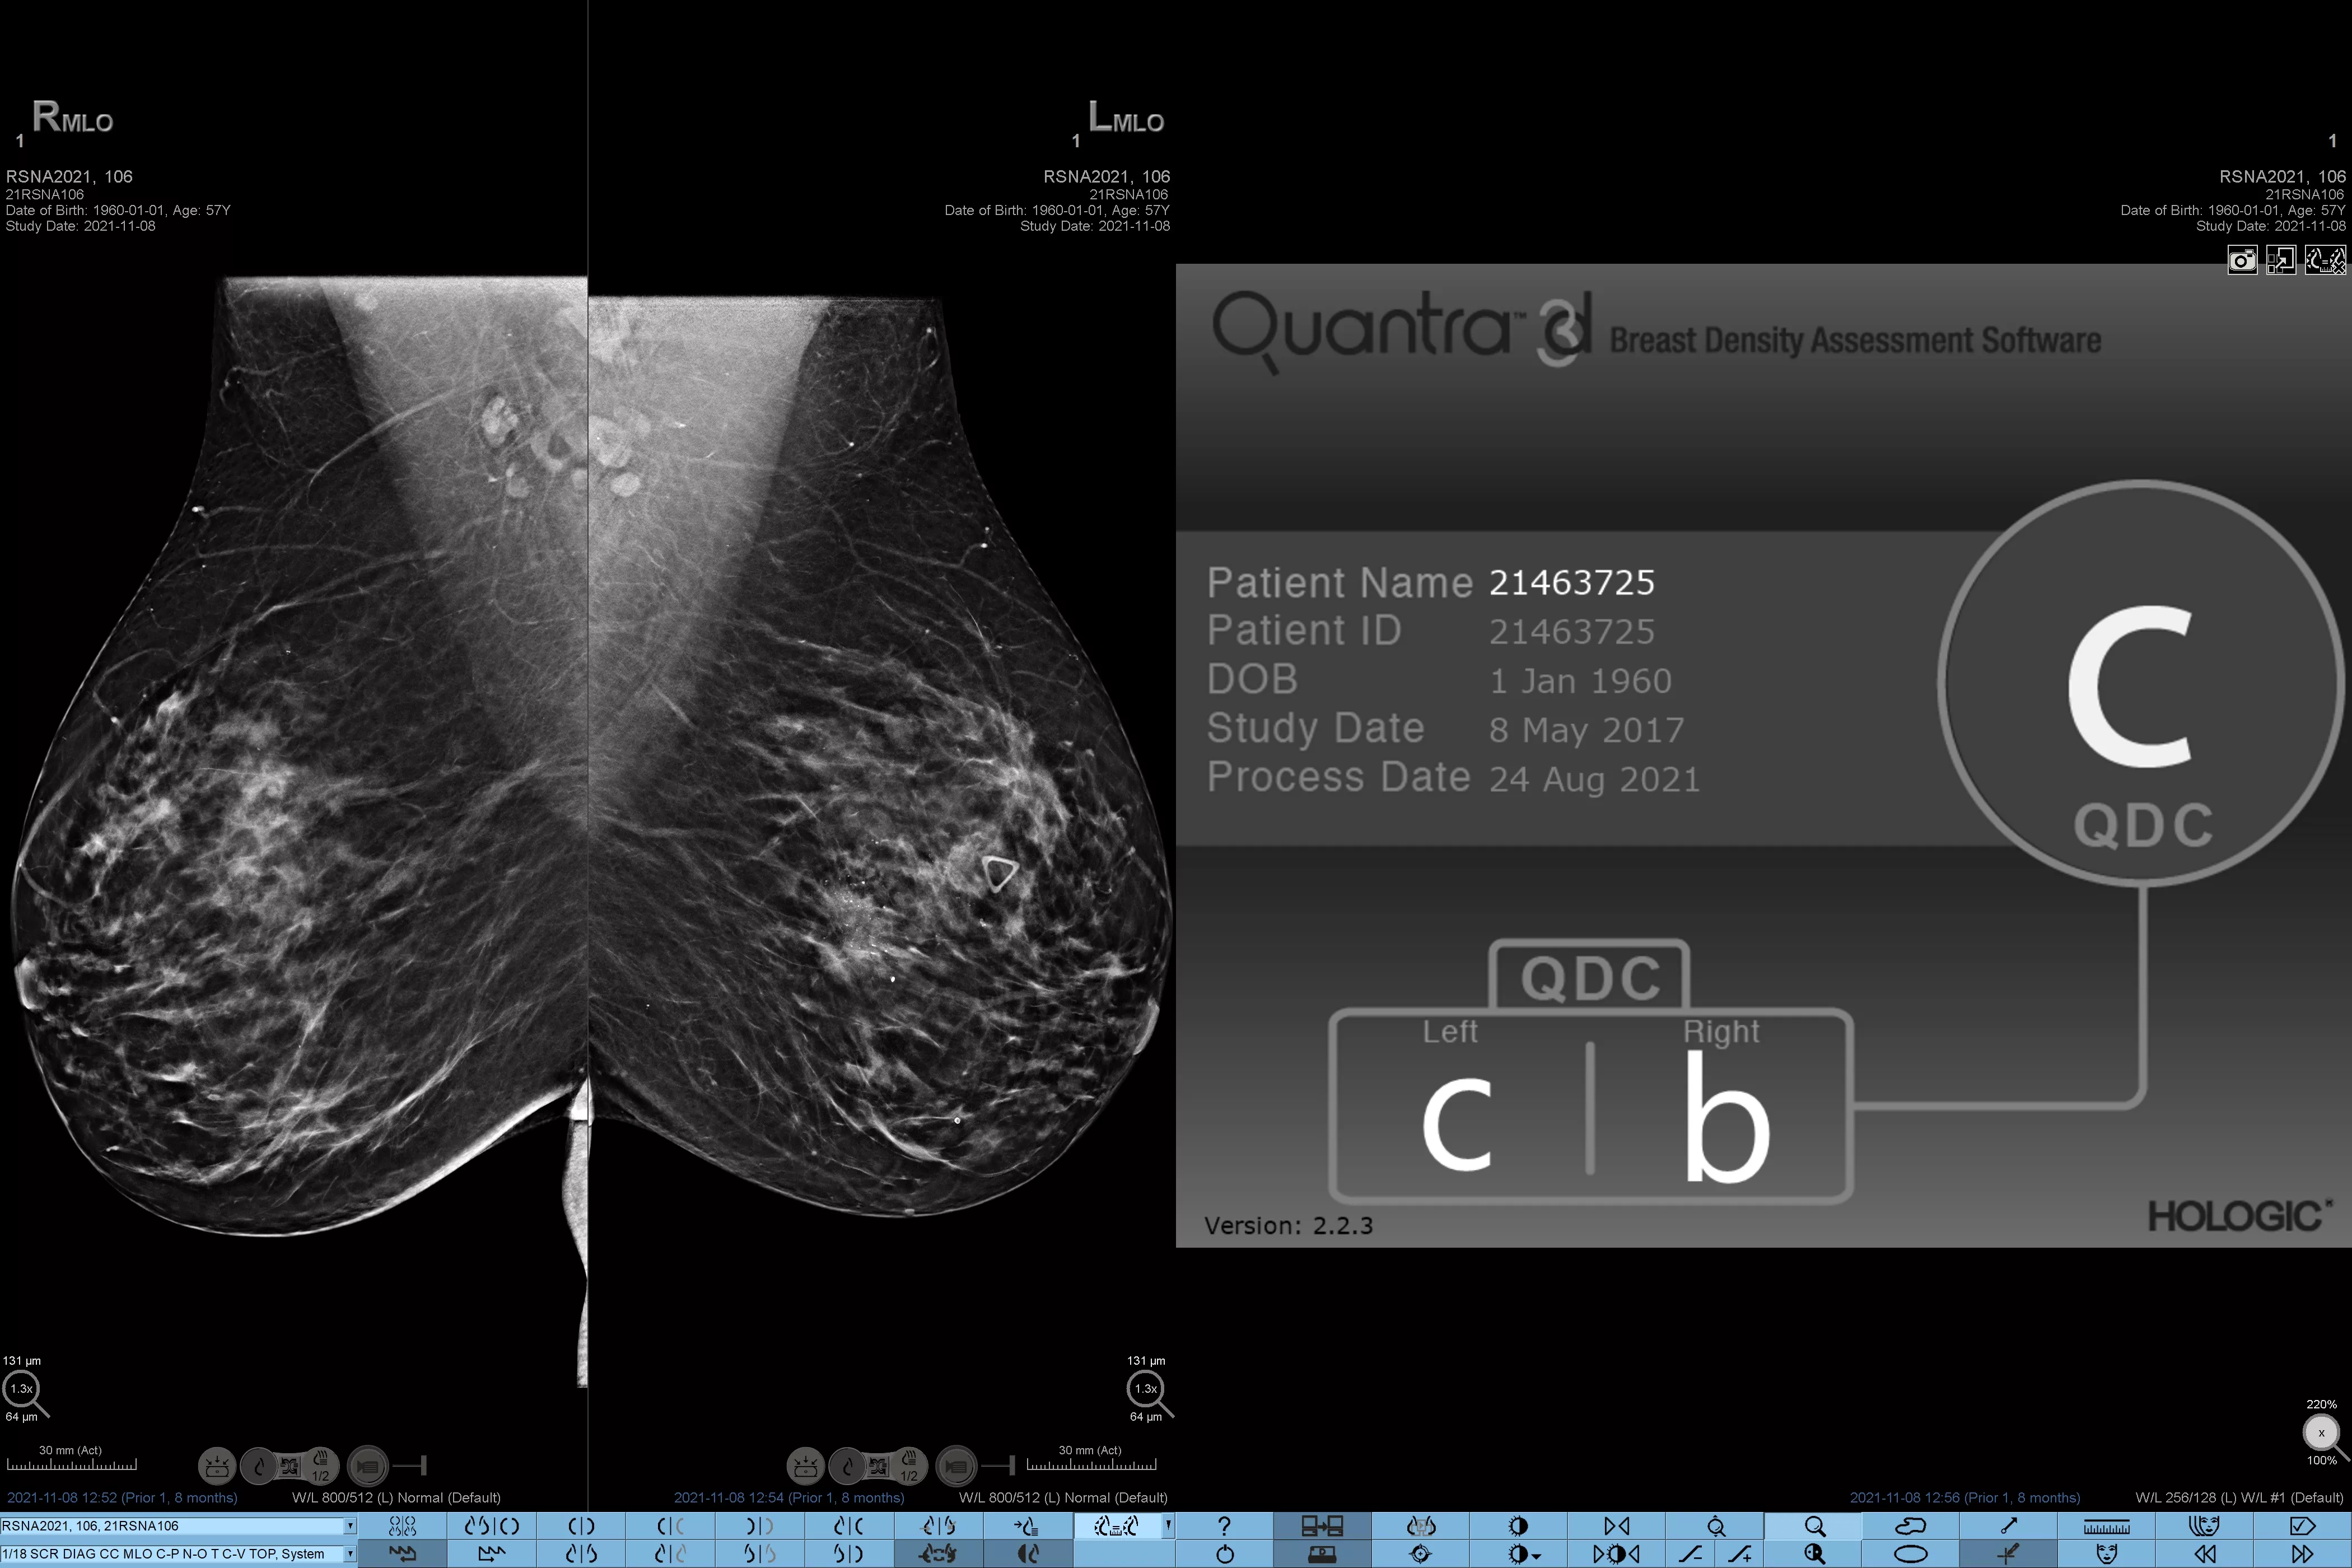

Eine höhere Brustdichte geht bekanntlich mit einem höheren Brustkrebsrisiko einher.1 Eine präzise, objektive Analyse ist daher entscheidend. Die durch maschinelles Lernen unterstützte Software der Quantra Technologie analysiert sowohl 2D™- als auch Tomosynthese-Bilder in Bezug auf Verteilung und Textur des Parenchymgewebes. Sie teilt die Brüste entsprechend der Leitlinie der 5. Auflage des BI-RADS Atlas des American College of Radiology (ACR) nach ihrer Zusammensetzung in vier Brustdichte-Kategorien ein.2

Objektiver Machine-Learning-Algorithmus, der die Brustdichte-Kategorie auf Basis der Analyse von Textur und Muster des Brustgewebes zuordnet.

Der objektive Algorithmus der Quantra-Software analysiert sowohl 2D- als auch Tomosynthese-Bilder und unterstützt Sie bei Ihrer Analyse durch:

• Unabhängigkeit von subjektiver visueller Beurteilung für eine konsistentere und zuverlässigere Einstufung.*

*Die Scores basieren auf den ACR BI-RADS-Kategorien nach den revidierten Leitlinien der 5. Auflage des vom American College of Radiology (ACR) herausgegebenen BI-RADS-Atlas. Dadurch werden Struktur und Textur im Vergleich zum Volumen bei der Dichtebestimmung berücksichtigt.